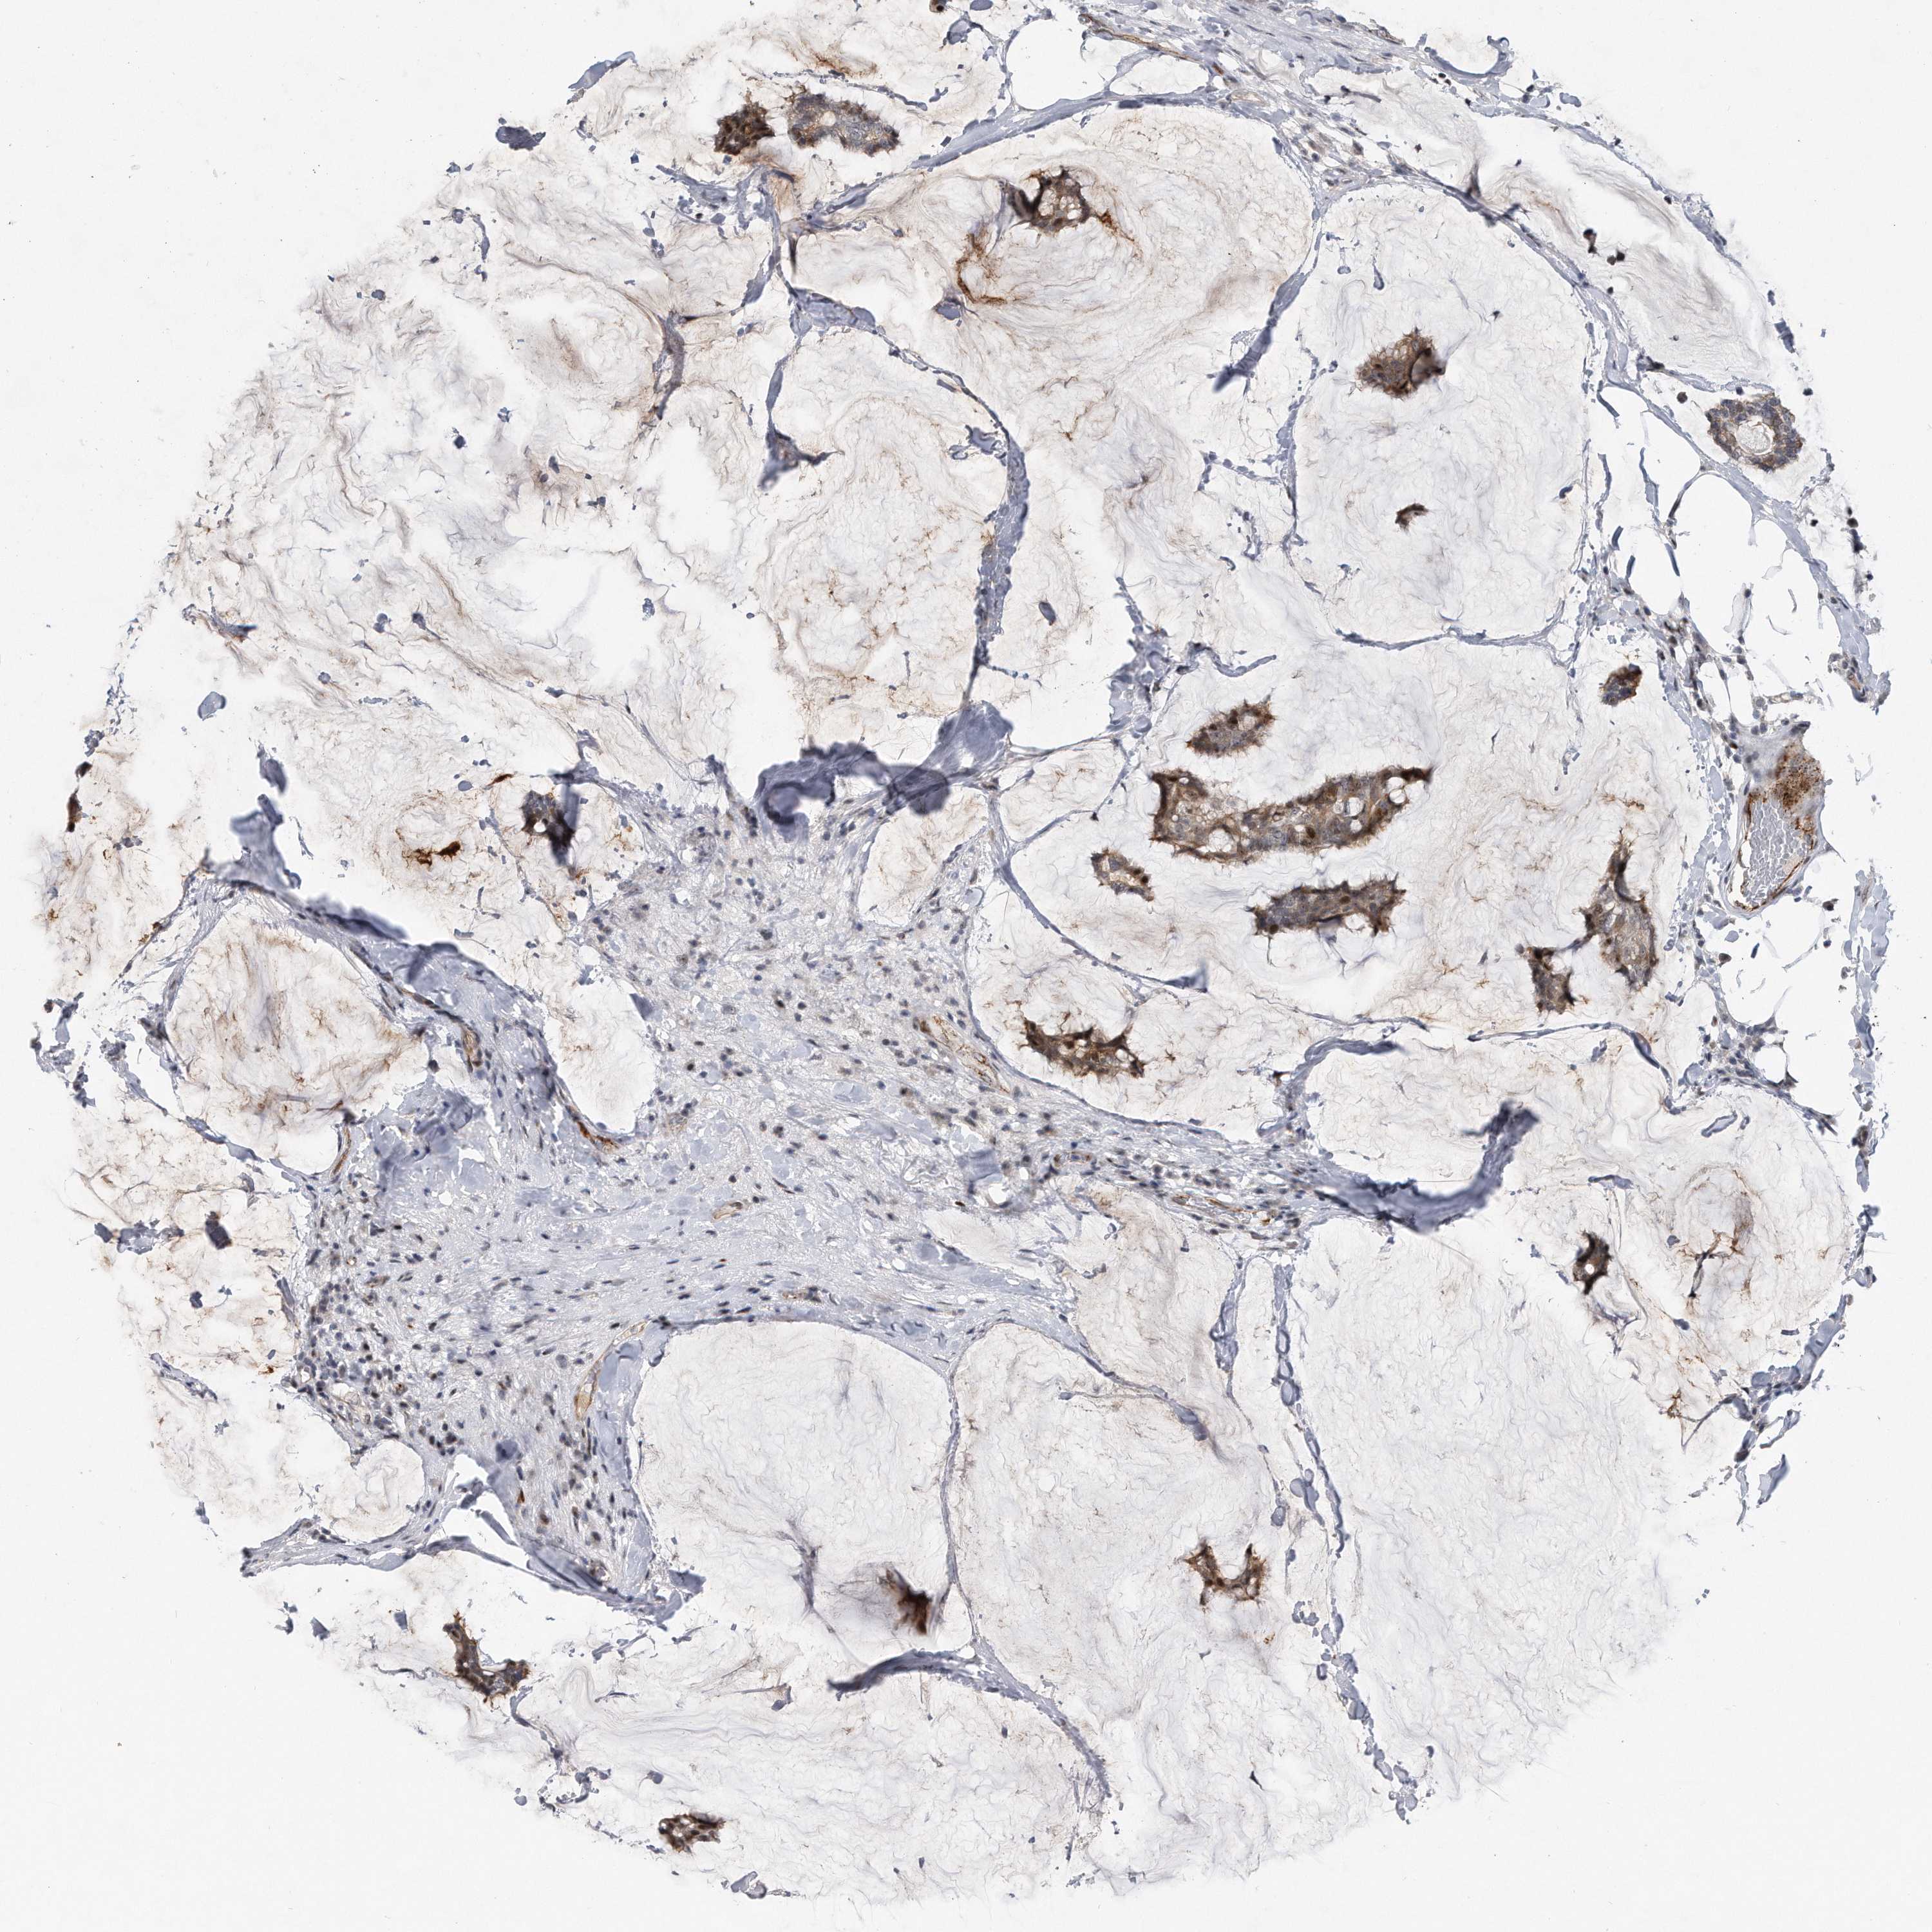

BRCA TCGA BRCA VALIDATION PROTEIN EXPRESSION

ANTIBODIES

AND

VALIDATION